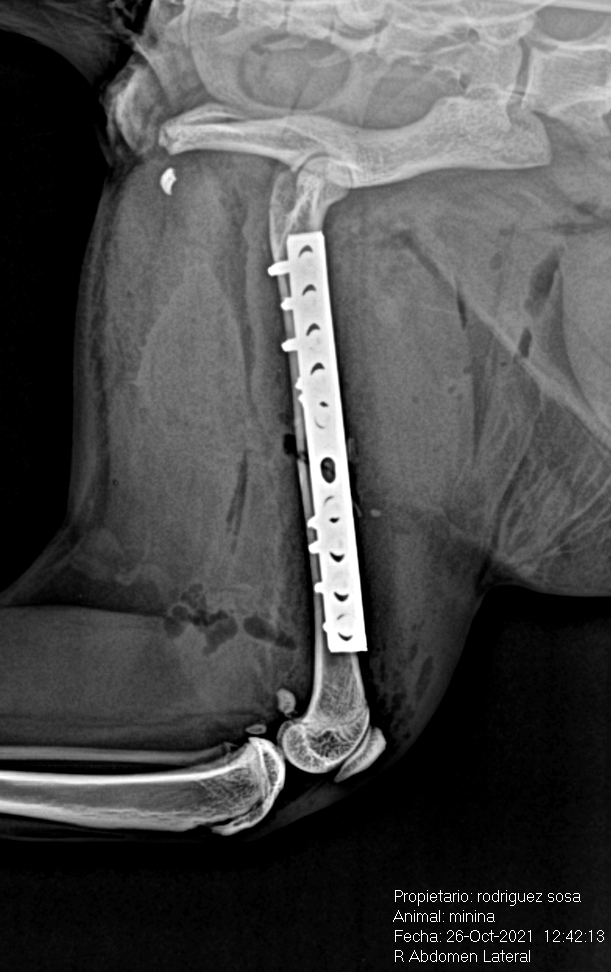

Fractura diafisaria distal de femur en un gato, tratada con placa y tornillos.